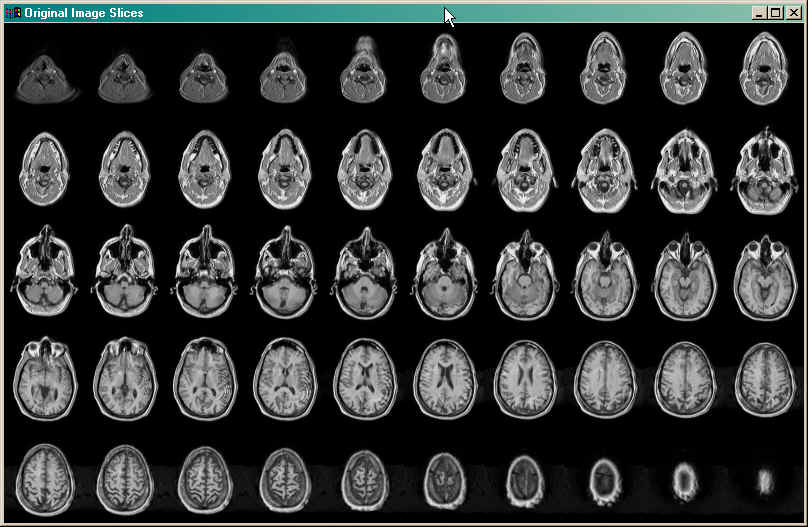

First, let's have a look at what the image slices themselves. Let's put them all in one window. Type this:

Window, Title='Original Image Slices', XSize=800, YSize=500, 1, XPos=0, YPos=0 LoadCT, 0 Device, Decomposed=0 FOR j=0,49 DO TV, volume[*,*,j], j

The results are seen in the figure below.